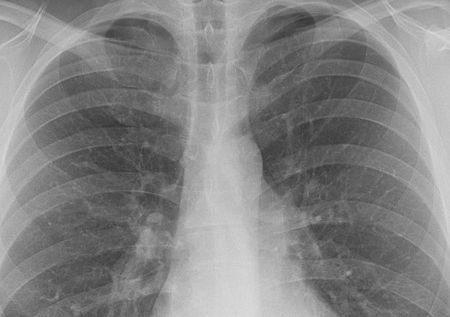

Szeptember 2-5 és 8-9 között reggel 8 órától délután 6 óráig várják az embereket tüdőszűrésre az Egészségklubba, a Szentendrei út 24 számba.

Kép: telki.hu